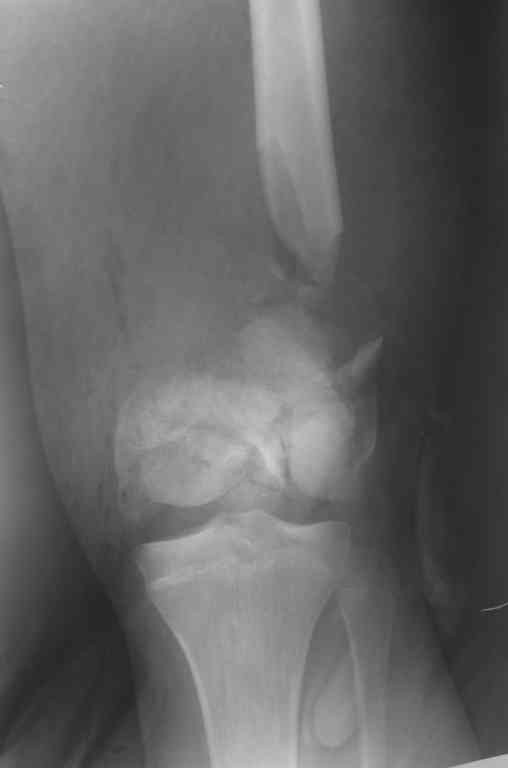

Внутрисуставной перелом бедренной кости |

Уважаемые коллеги! Хотелось бы услышать ваше мнение по тактике лечения перелома бедра.

Пациент 17 лет. Травма 07.10.2006 - попал под грузовик. Рана на бедре зажила первичным натяжением. Мы рассматриваем следующие варианты: открытая репозиция + 1)остеосинтез аппаратом внешней фиксации; или 2)фиксация пластиной LCP. Ваши предложения? Как бы вы поступили с имеющимся дефектом бедренной кости?